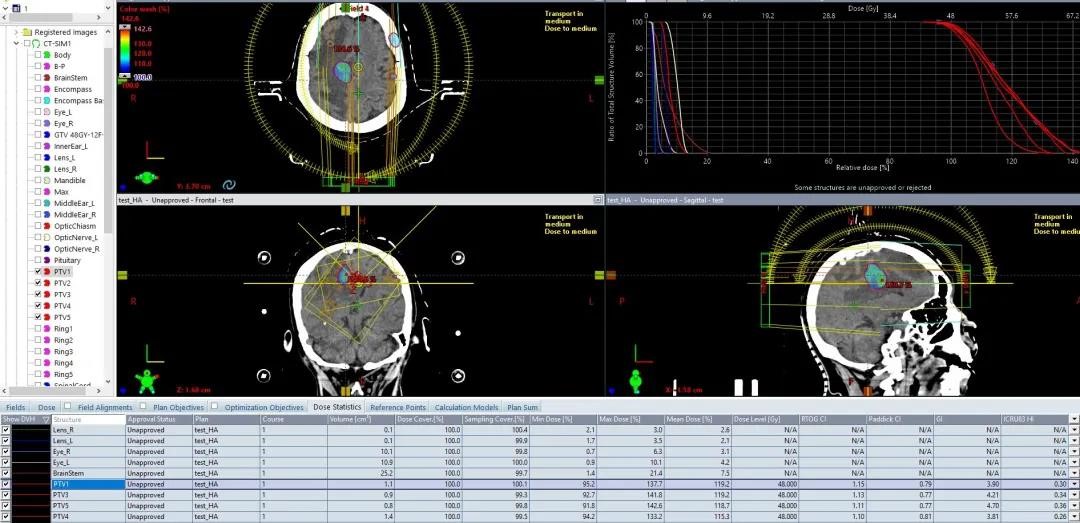

02 多发脑转移

肺癌脑多发转移,5个靶点,最大直径3cm,48Gy/12F,

CI:1.14、5mm外跌落到50%处方剂量

HyperArc剂量跌落明显优于传统非共面VMAT治疗,

而且对于多发脑转移,各靶点单独优化,效果更好